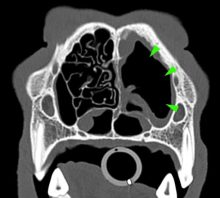

What’s your diagnosis? Computed Tomography Case 6

Diagnostic Imaging |

How Computed Tomography can help us in the diagnosis of diseases of the head An 11-year-old cocker spaniel was ...